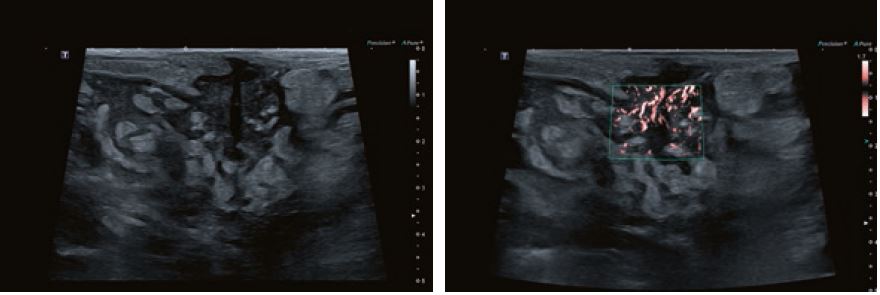

Випадок 3

Собака змішаної породи, 11 років; Гематурія; високо васкуляризоване циркулярне звуження сечового міхура з центральною вхідною судиною; хірургічне видалення з подальшою фотодинамічною терапією осередку пухлини потужністю три вати; НР: перехідно-клітинна карцинома; контрольне УЗД через шість місяців - в нормі.

Передова технологія Aplio Wall Motion Tracking забезпечує миттєвий візуальний і кількісний доступ до глобальної та локальної динаміки руху стінок міокарда у 2D і 3D. Крім того, супермікросудинна візуалізація (SMI) - це технологія, яка розширює діапазон видимого кровотоку і забезпечує візуалізацію низького мікросудинного потоку, який раніше не був видимий при ультразвуковому дослідженні. У порівнянні зі звичайними доплерівськими технологіями, перевагами SMI є доплерівська візуалізація з наднизьким кровотоком з високою частотою кадрів, високою роздільною здатністю, високою чутливістю і чудовим усуненням артефактів руху від рухомого об'єкту. Це дає клініцистам новий спосіб виявлення найдрібніших судин, що дозволяє проводити більш ефективну і точну діагностику при оцінці уражень, запальних захворювань і пухлин. SMI пропонує ефективний інструмент для оцінки стану плоду та моніторингу пацієнта на етапі лікування. SMI забезпечує клінічну впевненість шляхом ранньої діагностики аномалій і дає життєво важливе уявлення про мікросудинну систему, що допомагає у встановленні діагнозу.